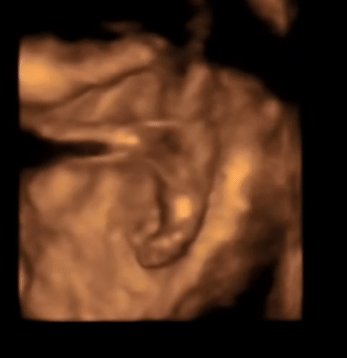

四维照片大家帮忙看看是不是男宝宝生殖器 点击展开 母婴用户192076383 2014-11-09 09:47 满意回答 挺像的 匿名用户 2014-11-09 10:01 宝宝知道提示您:回答为网友贡献,仅供参考。 相关问题 有医生可以帮我看看做四维彩超拍到了像是男孩的生殖器 晒晒俺家宝宝的四维彩超,宝宝的第一张照片呀,嘿嘿,不知道男宝女宝 宝妈你们的呢 晒晒俺家宝宝的四维彩超,宝宝的第一张照片呀,嘿嘿,不知道男宝女宝 宝妈你们的呢